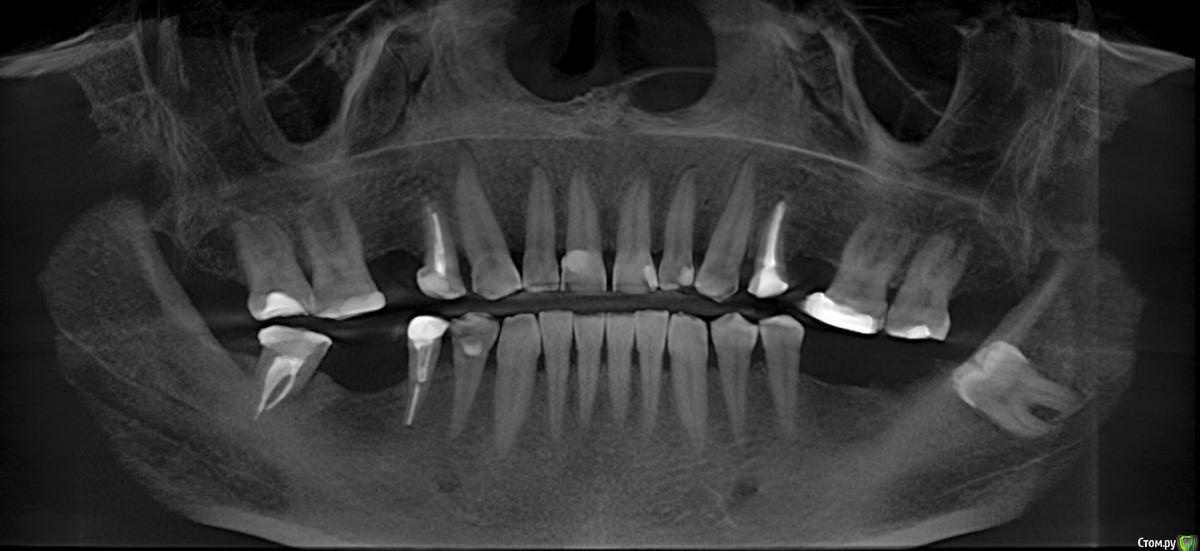

Опустился зуб, недостаточно места для импланта. Усечение гребня?

опустились 26, 27. Ортодонт не рекомендует "вколачивание".

Хотелось бы сохранить 26 и 27.

Предлагается усечение нижнего альвеолярного гребня для того, чтобы поставить импланты 36 и 37 и коронки минимально допустимой высоты.